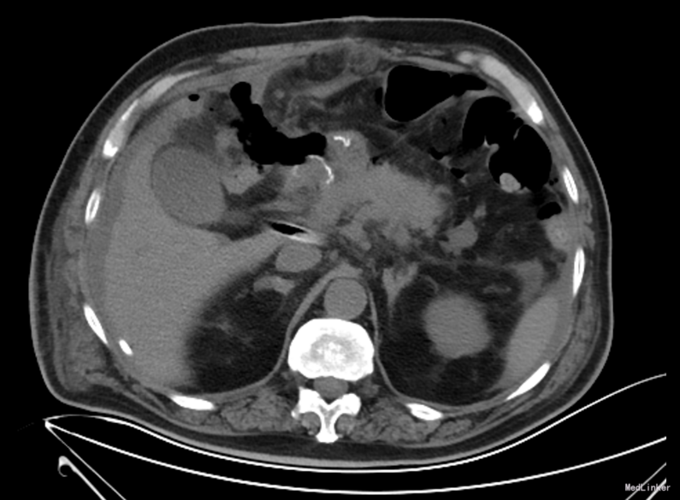

诊断:胃癌;中度贫血;冠心病陈旧性心肌梗死;高血压2级(极高危);冠脉造影及支架植入术后 治疗:全麻下行胃癌根治切除(D2)、Billorth-I式吻合、空肠营养造瘘术,手术顺利,术后恢复可,术后第7天,患者突然出现右侧腹部疼痛,后转移至下腹及左侧髂腹部等,吻合口后引流管引流出暗黄色浑浊液体,留置胃管后引流出同性质液体,考虑吻合口瘘,复查全腹CT平扫,肝周积液较前增多。请介入科行肝周积液的穿刺引流,同时经空肠营养管予肠内营养,但患者仍持续高热,经介入科第二次穿刺引流后,患者体温由39.5℃逐渐下降至正常。